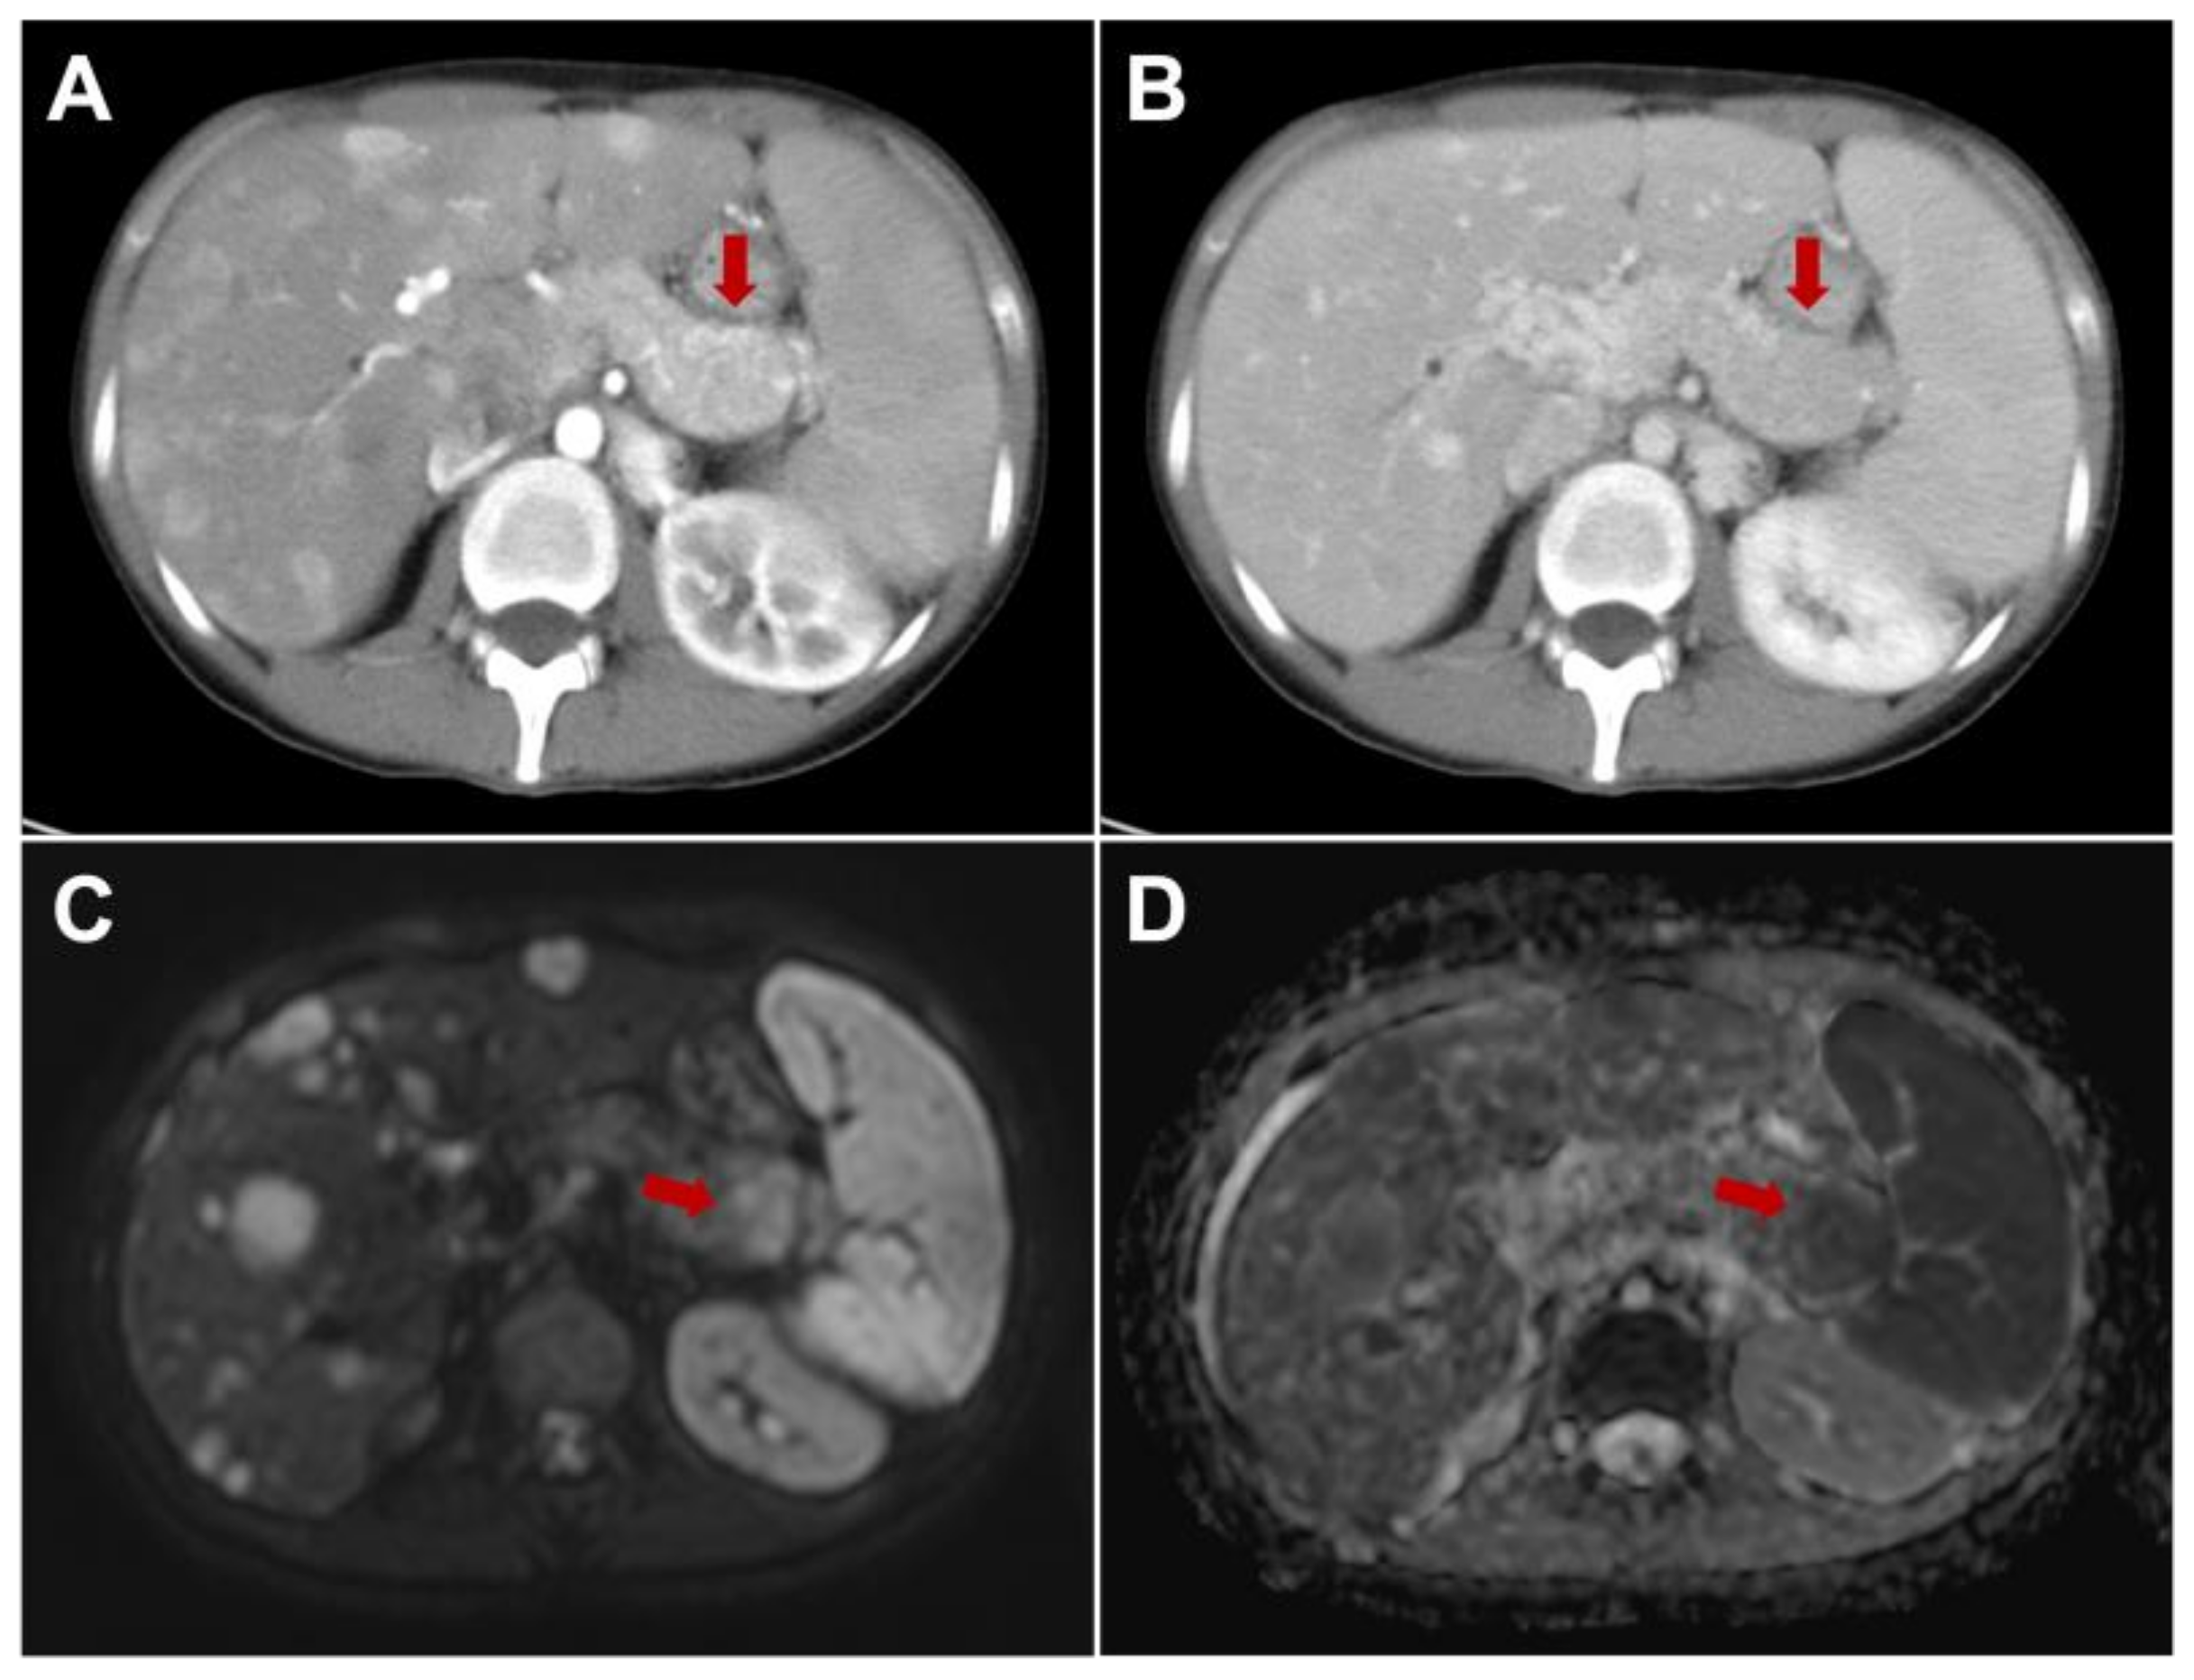

Multiparametric MRI represents a valid imaging method to cover the main gaps of contrast-enhanced CT, especially in tumor detection and in M-staging; these aspects are mandatory to choose the best therapeutic options and for surgical planning: Figure 4 [27,52]. In particular, the detection rate of morphological sequences in small panNENs is similar to contrast enhanced CT, but the implementation of diffusion-weighted images improved the sensitivity in both panNENs detection and in assessment of liver metastases [100]. Furthermore, the use of hepatobiliary phase with Gd-EOB-DTPA should always be considered to have a complete evaluation of liver involvement, and by using the combined set of diffusion-weighted images and hepatobiliary phase, allows high value of sensitivity and specificity to be achieved in the step of diagnosis and during follow-up [101]. Recently, MRI was investigated to identify high-risk patients, evaluating the features correlated with tumor grading and early progressive disease after surgery. Indeed, Canellas R. et al. [102] demonstrated that MRI could be used to predict poor prognosis in the case of tumor size major of 2 cm, non-bright signal of lesions on T2, in the presence of both duct dilatation and restricted diffusion.

Figure 4.

A 35-year-old female with atypical metastatic pancreatic neuroendocrine neoplasm of the tail, difficult to identify in contrast-enhanced CT due to the iso-enhancement in arterial ((A), arrow) and portal ((B), arrow) phase. It was detected by MRI by using diffusion-weighted images, showing hyperintensity on the DWI ((C), arrow) and low signal intensity on the ADC map ((D), arrow).